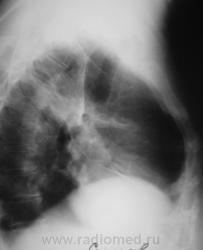

Пациентка обратилась к терапевту по поводу грудных жалоб, направлена на рентгенографию ОГК с диагнозом "Пневмония?"

После проведения противовоспалительной терапии произведен рентген-контроль.

Произведена стандартная рентгенография.

"Прямая" проекция.

А не ателектаз S3? И легкое уменьшено, и высока междолевка, и в корне что-то?

Вот, вот и я о том же - в корне-то кругляк.

Верхняя доля уменьшена в объёме, средняя, вроде-бы увеличена в объёме?

А, что-же тут рентгенологически, свидетельствует о ТЭЛА?

Гомогенное затенение в пределах сегмента, в форме треугольника, основанием прилегающего к плевре, вершиной обращённого к корню; высокое стояние купола диафрагмы на стороне поражения; полнокровие корней лёгких --- разве нет? При определённой клинической картине было бы весьма показательно, при отсутствии её --- сомнительно.

Верхняя доля правого лёгкого бесспорно уменьшена. Но вот корень… картина не похожа на центральный рак. А на инфаркт-пневмонию не похожа клиника. Возможно будет результат КТ.